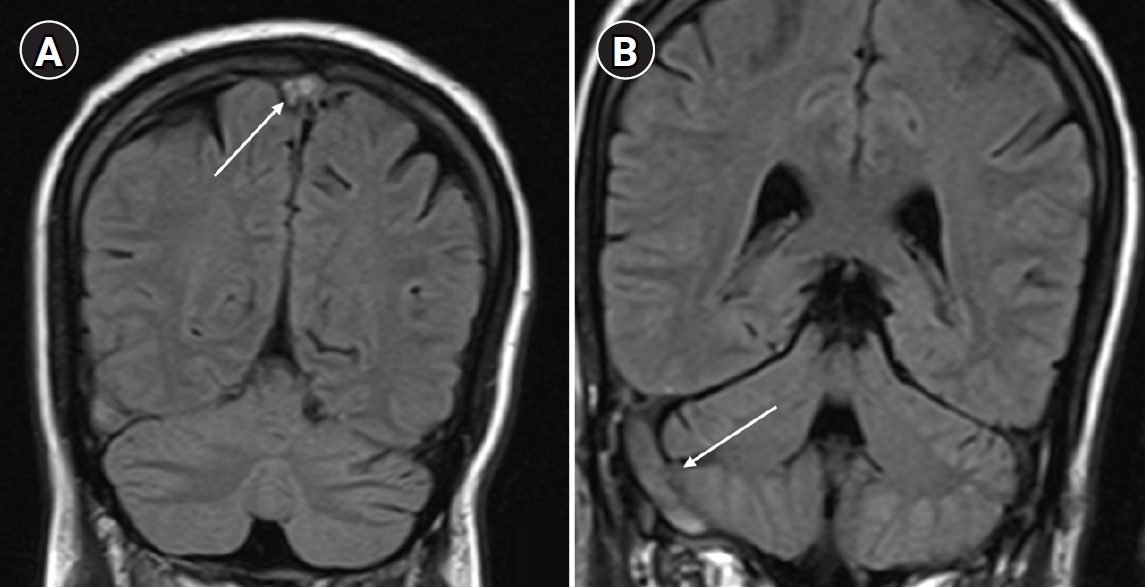

Arterial blood gas analysis performed on room air showed no hypoxemia, with a partial pressure of oxygen of 86 mm Hg. Brain magnetic resonance imaging (MRI) with venography revealed cerebral venous sinus thrombosis involving the superior sagittal sinus, right transverse sinus, and sigmoid sinus (Fig. 1).

Fig. 1.

(A) Coronal and sagittal magnetic resonance imaging (MRI) brain images showing thrombosis of the superior sagittal sinus (arrow). (B) MRI brain image showing thrombosis of the right transverse sinus and sigmoid sinus (arrow).